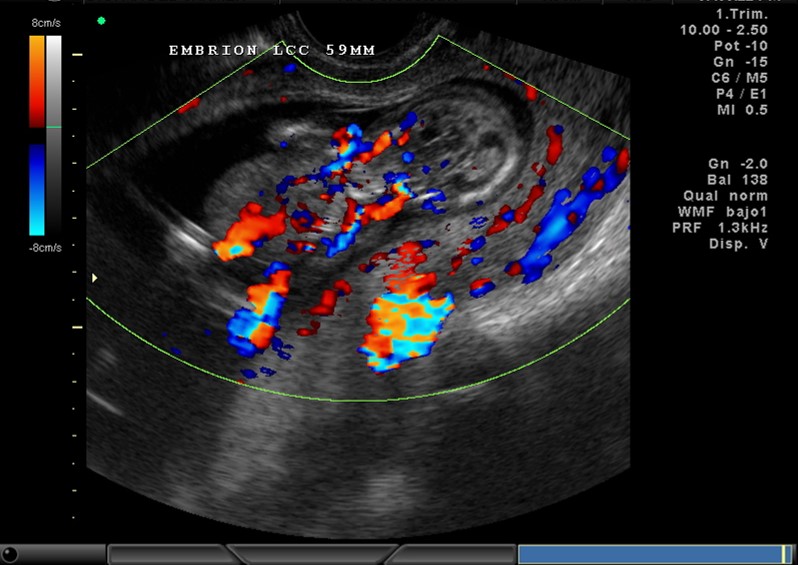

2D Y COLOR VASOS, 11.5 SEMANAS

2D Y COLOR ABDOMEN, CORDON 12 SEMANAS